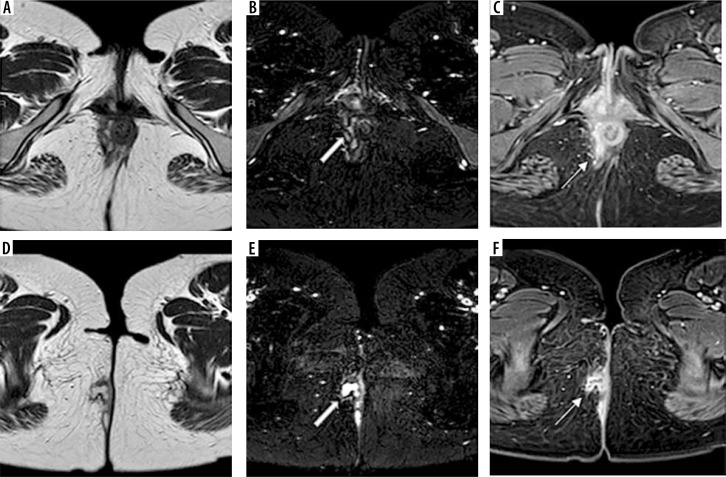

目的:肛瘘的诊断对外科医生来说是一个挑战。众所周知,磁共振成像(MRI)在其中起着重要作用。与二维(2D)序列相比,新的三维MRI序列VISTA(体积同位素涡轮自旋回波采集)可以改善肛周瘘的检测和表征。本研究的目的是通过对比增强(CE) 3D T1序列THRIVE (T1加权高分辨率各向同性体积检查)作为参考标准,比较新的3D MRI序列VISTA与广泛常规使用的T2 FSE脉冲序列在描述和表征肛周瘘方面的诊断性能。材料和方法:40名成年患者被纳入这项前瞻性研究。他们接受了常规T2 TSE和CE 3D T1 THRIVE序列的MRI肛周检查,并添加了新的3D MRI序列VISTA。T2、3D VISTA和(CE) 3D T1序列THRIVE影像分别由两名放射科医师评估,用于检测和表征肛周瘘,然后以(CE) 3D T1序列THRIVE作为参考,比较T2和3D VISTA序列。每个序列的敏感性、特异性和准确性由两名读取器计算。结果:阅读器1对3D VISTA的敏感性、特异性和准确性分别为92.5%、90.5%和93.6%,对T2 FSE的敏感性、特异性和准确性分别为84.1%、83.7%和87.3%。阅读器2对3D VISTA的敏感性、特异性和准确性分别为91.5%、92.8%和94.8%,对T2 FSE的敏感性、特异性和准确性分别为82.9%、84.5%和86.7%。结论:以CE 3D T1序列THRIVE为参照标准,与常规使用T2 FSE序列相比,肛周区3D VISTA脉冲序列在检测和表征肛周瘘方面具有更好的诊断性能。

Purpose: Diagnosis of perianal fistula represents a challenge for surgeons. It is well known that magnetic resonance imaging (MRI) plays an important role in that. The new 3D MRI sequence VISTA (Volume ISotopic Turbo spin echo Acquisition) can improve detection and characterization of perianal fistula compared with two-dimensional (2D) sequences. The aim of the study was to compare the diagnostic performance of the new 3D MRI sequence VISTA with the widely routinely used T2 FSE pulse sequence in depiction and characterization of perianal fistula by using the contrast-enhanced (CE) 3D T1 sequence THRIVE (T1-weighted high-resolution isotropic volume examination) as a reference standard.

Material and methods: Forty adult patients were enrolled in this prospective study. They underwent MRI perianal region examination using routine T2 TSE and CE 3D T1 sequence THRIVE with addition of the new 3D MRI sequence VISTA. T2, 3D VISTA and (CE) 3D T1 sequence THRIVE images were evaluated by two radiologists separately for detection and characterization of perianal fistula, then comparison between of T2 and 3D VISTA sequences was done using (CE) 3D T1 sequence THRIVE as a reference. Each sequence sensitivity, specificity and accuracy were calculated by both readers.

Results: For reader 1, the sensitivity, specificity and accuracy were 92.5%, 90.5% and 93.6% for 3D VISTA and 84.1%, 83.7% and 87.3% for T2 FSE. For reader 2, the sensitivity, specificity and accuracy were 91.5%, 92.8% and 94.8% for 3D VISTA and 82.9%, 84.5% and 86.7% for T2 FSE.